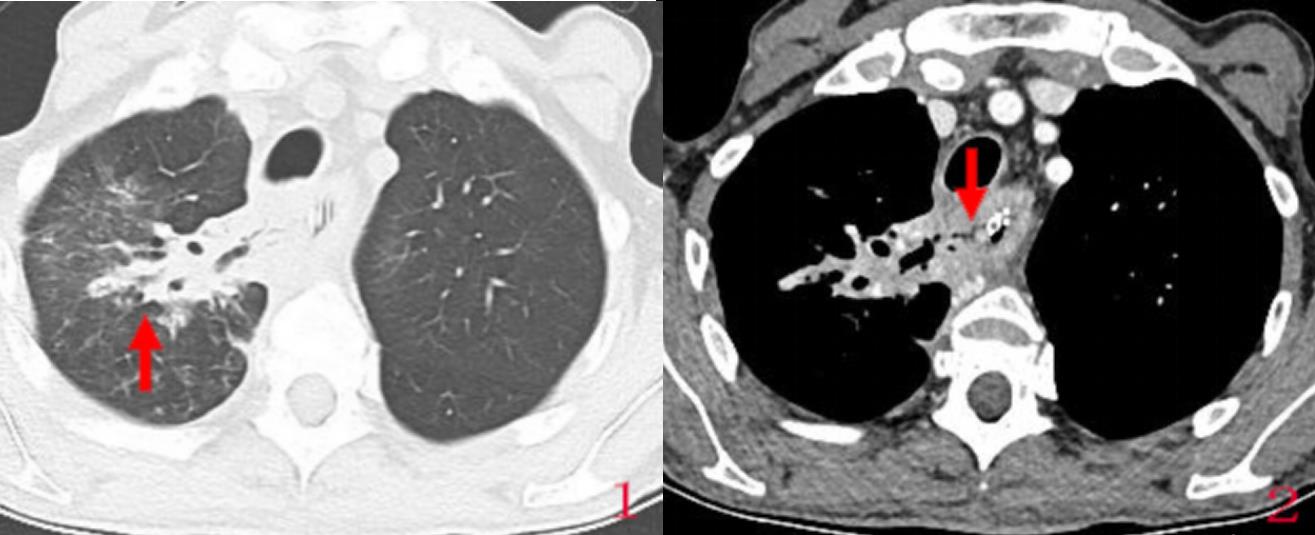

患者65岁,老年男性,以“发现食管癌4月余,进食水呛咳伴脓痰1月”入院。入院后完善血液学及影像学检查;行胸部CT见下图:

图1箭头示患者右肺上叶炎症明显;图2加强CT可见食管上段食管壁明显增厚伴强化,可见一裂隙瘘道影由贯穿食管和气管(箭头示);考虑为食管癌伴食管气管瘘。